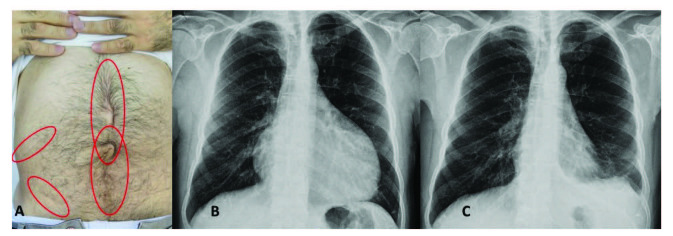

腹膜发作开始局限并迅速蔓延至整个腹部。腹膜炎症会导致典型的肠梗阻症状,患者会遭受严重的胃痛。体格检查显示腹部肌肉僵硬、反跳痛和肠鸣音消失——临床上这种紧急情况与急腹症的手术原因无法区分。因此,隐匿性腹部手术史在良性阵发性腹膜炎患者中很常见(图 1A)。在疑似病例中,影像学检查可能有助于排除手术病理。腹部发作后可能会出现轻度反弹性腹泻。尽管有戏剧性的表现,但腹膜炎的所有体征和症状在 24-72 小时内有效消退,没有后遗症,尽管慢性腹水和腹膜粘连的报道很少。

图1:(A) 一位因多次腹部手术而留下疤痕的患者,(B) 胸部 X 光片显示大量心包积液,(C) 同一患者用阿那白滞素治疗后的胸部 X 光片。

不到 50% 的患者会出现胸膜炎发作,表现为突然发作的单侧胸膜炎,可能单独发生,也可能与腹膜炎和发热同时发生。患者描述了典型的严重胸膜炎性胸痛,经检查,他们的胸部患侧呼吸音减弱。胸部 X 光片可能显示肋膈角有少量渗出液。发作通常会在一到三天内有效消退。

心包炎是一种罕见病症,见于 1%–2% 的患者。心包炎会出现胸骨后胸痛和呼吸困难等症状。心包填塞可能很少发生。心电图显示 ST 段抬高,胸部 X 光片可能显示心脏轮廓的短暂扩大(图 1B 和 1C),超声心动图显示心包积液。在极少数情况下,反复性心包炎可能是良性阵发性腹膜炎的少有表现,这可能与特发性心包炎相混淆 。